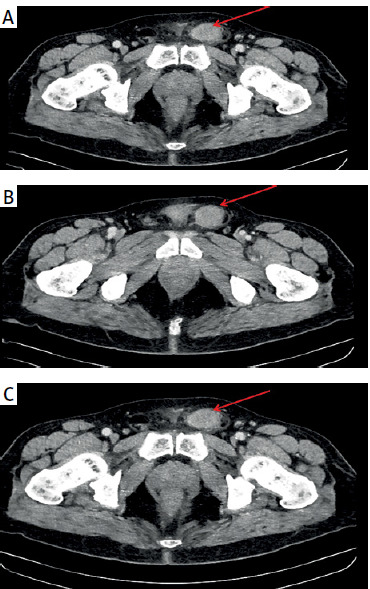

Undifferentiated pleiotropic spermatic duct sarcoma: a surgical surprise in the inguinal canal that calls for attention.

未分化多性精管肉瘤:腹股沟管的手术意外,需要引起注意。